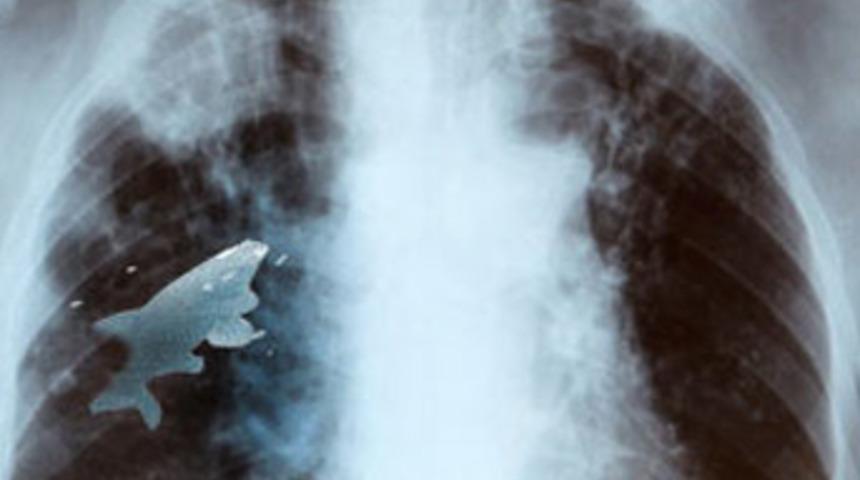

Hindistan’da bir çocuğun nehir kenarında oynarken yuttuğu balık ciğerine kaçtı. Nefes darlığı nedeniyle hastaneye kaldırılan çocuğun ciğerindeki balık, yapılan operasyonla canlı olarak çıkarıldı.

Nehir kenarında arkadaşlarıyla oynayan 12 yaşındaki Anil Barela isimli çocuk, 9 santimetre büyüklüğünde bir balık yuttu. Times of India gazetesinin haberine göre çocuğun daha önce de birkaç kez canlı balık yuttuğu ancak bu kez balığın başka bir yöne giderek çocuğun ciğer bölgesinde sıkışıp kaldığı belirtildi.

Balığın sürekli hareket etmesi nedeniyle nefes almakta güçlük yaşamaya başlayan çocuğun kanındaki oksijen oranının da ciddi oranda düşüş göstermesi sonucunda çocuk x-ray cihazından geçirildi.

Çekimlerde ciğerlerinde dolaşan balık tespit edilince çocuk hemen ameliyata alındı. Yaklaşık 45 dakikalık operasyonun ardından balık, canlı olarak çıkarıldı.